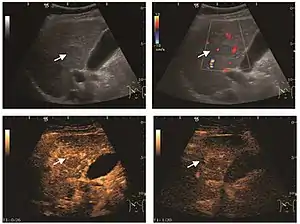

Liver metastases

US examination is required to detect liver metastases in patients with oncologic history. In addition, the method can incidentally detect metastases in asymptomatic patients. Early identification (small sizes, small number) is important to establish an optimal course of treatment which can be complex (chemotherapy, radiofrequency ablation, surgical resection) but welcomed. In addition, discrimination of synchronous lesions that have a different nature is also important knowing that up to 25–50% of liver lesions less than 2 cm detected in cancer patients may be benign . US sensitivity for metastases detection varies depending on the examiner's experience and the equipment used and ranges between 40 and 80% . Sensitivity is conditioned by the size and acoustic impedance of the nodules. For a lesion diameter below 10 mm US accuracy is greatly reduced, reaching approx. 20%. Other elements contributing to lower US performance are: excessive obesity, fatty liver disease, hypomobility of the diaphragm, and certain patterns of hyperechoic or isoechoic metastases that can be overlooked or can mimic benign conditions. Conventional US appearance of metastases is uncharacteristic, consisting of circumscribed lesions, with clear, imprecise or "halo" delineation, with homogeneous or heterogeneous echo pattern. They can be single (often liver metastases from colonic neoplasm) or multiple. Echogenity is variable. When increased, they can compress the bile ducts (which may be dilated) and the liver vessels. Liver involvement can be segmental, lobar or generalized. In this situation a pronounced hepatomegaly occurs. Generally, metastases have non-characteristic Doppler vascular pattern, with few exceptions (carcinoid metastases). Cyst-adenocarcinoma metastases due to semifluid content may have a transonic appearance. When increasing, they can result in central necrosis. CEUS examination is a real breakthrough for detection and characterization of liver metastases.

Increased performance is based on identifying specific vascular patterns during the arterial phase and seeing metastases in contrast to normal liver parenchyma during the sinusoidal phase. CEUS increased accuracy is due to the different behavior of normal liver parenchyma (captures CA in Kuppfer cells) against tumor parenchyma (does not contain Kuppfer cells, therefore CEUS appearance is hypoechoic). To this adds the particularities of intratumoral circulation represented by a reduced arterial bed compared to that of the surrounding normal liver and the absence of the portal vessels . In terms of vascularity, metastases can be hypovascular (in gastric, colonic, pancreatic or ovarian adenocarcinomas) with hypoechoic pattern during arterial phase, and similar during portal venous and late phases, respectively hypervascular (neuroendocrine tumors, malignant melanoma, sarcomas, renal, breast or thyroid tumors) with hyperechoic appearance during arterial phase, with washout during the portal venous phase and hypoechoic pattern 30 seconds after injection.